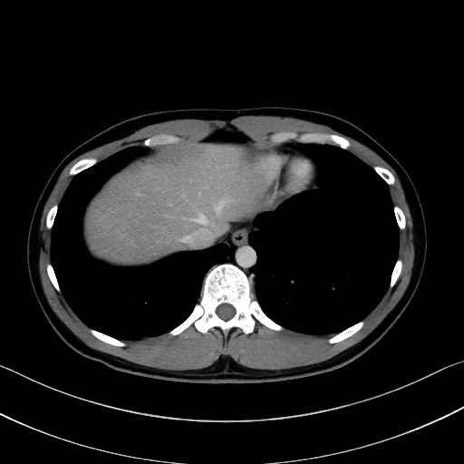

1. 体幹部(腹部・背部・後腹壁)の筋肉

広背筋 (Latissimus dorsi)

脊柱起立筋 (Erector spinae)

多裂筋 (Multifidus)